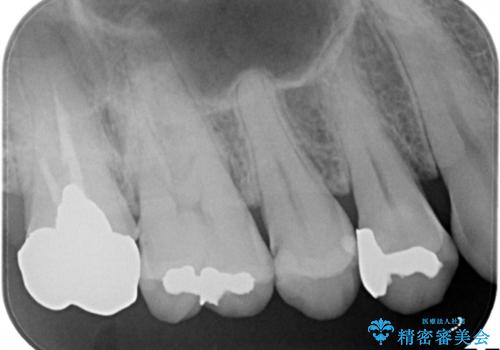

- 定期健診にてむし歯を認めたためゴールドインレーにて治療を行いました。

ゴールドインレーは適合が良く、割れることもないため、長期的に安定した治療法となります。